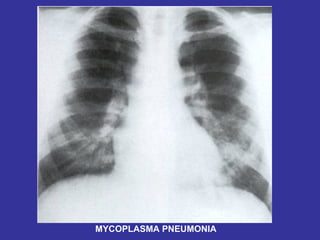

PNEUMONIA  Inflammation and infection of the lung parenchyma due to bacterial or viral  pathogens. Classified by anatomy:  Lobar, Interstitial, Bronchopneumonia Etiology: Viral:   Adenovirus, Influenza, RSV Bacterial:   Neonates:  GBS, Chlamydia, E. coli, Listeria monocytogenes  1month-6 years:  S. pneumonia, H. influenza Adolescents:  S. pneumonia, Mycoplasma pneumonia Immunocompromised:  Pseudomonas, klebsiela, Fungi, PCP

Epidemiology:   Children 2-4 years, are more susceptible than older children May follow epidemics of viral infection Winter/spring most common Day care/ kindergarten S/S:   Tachypnea,  dyspnea,  cough,  intercostal retractions, nasal flaring,  grunting,  fever,  accessory resp. muscles usage,  chest pain,  lethargy,  hypoxia, rales/crackles,  decreased  breath  sound/dullness to percussion (consolidation). LAB:   CBC:   WBC with left shift,  Blood culture (if severe picture),  Pleural fluid studies (effusion),  ABG  CXR:   Lobar consolidation ( S. pneumonia and H. influenza ),  Hilar adenopathy ( TB ),  Pneumatoceles ( S. aureus/G- ),  Bilateral diffuse infiltrate ( Mycoplasma ),  Abscess ( klebsiella ) Mycoplasma:  Presence of Cold agglutinin titers Prevention:   Pneumovax vaccine in immunocompromised children, SC Ds.

MYCOPLASMA PNEUMONIA